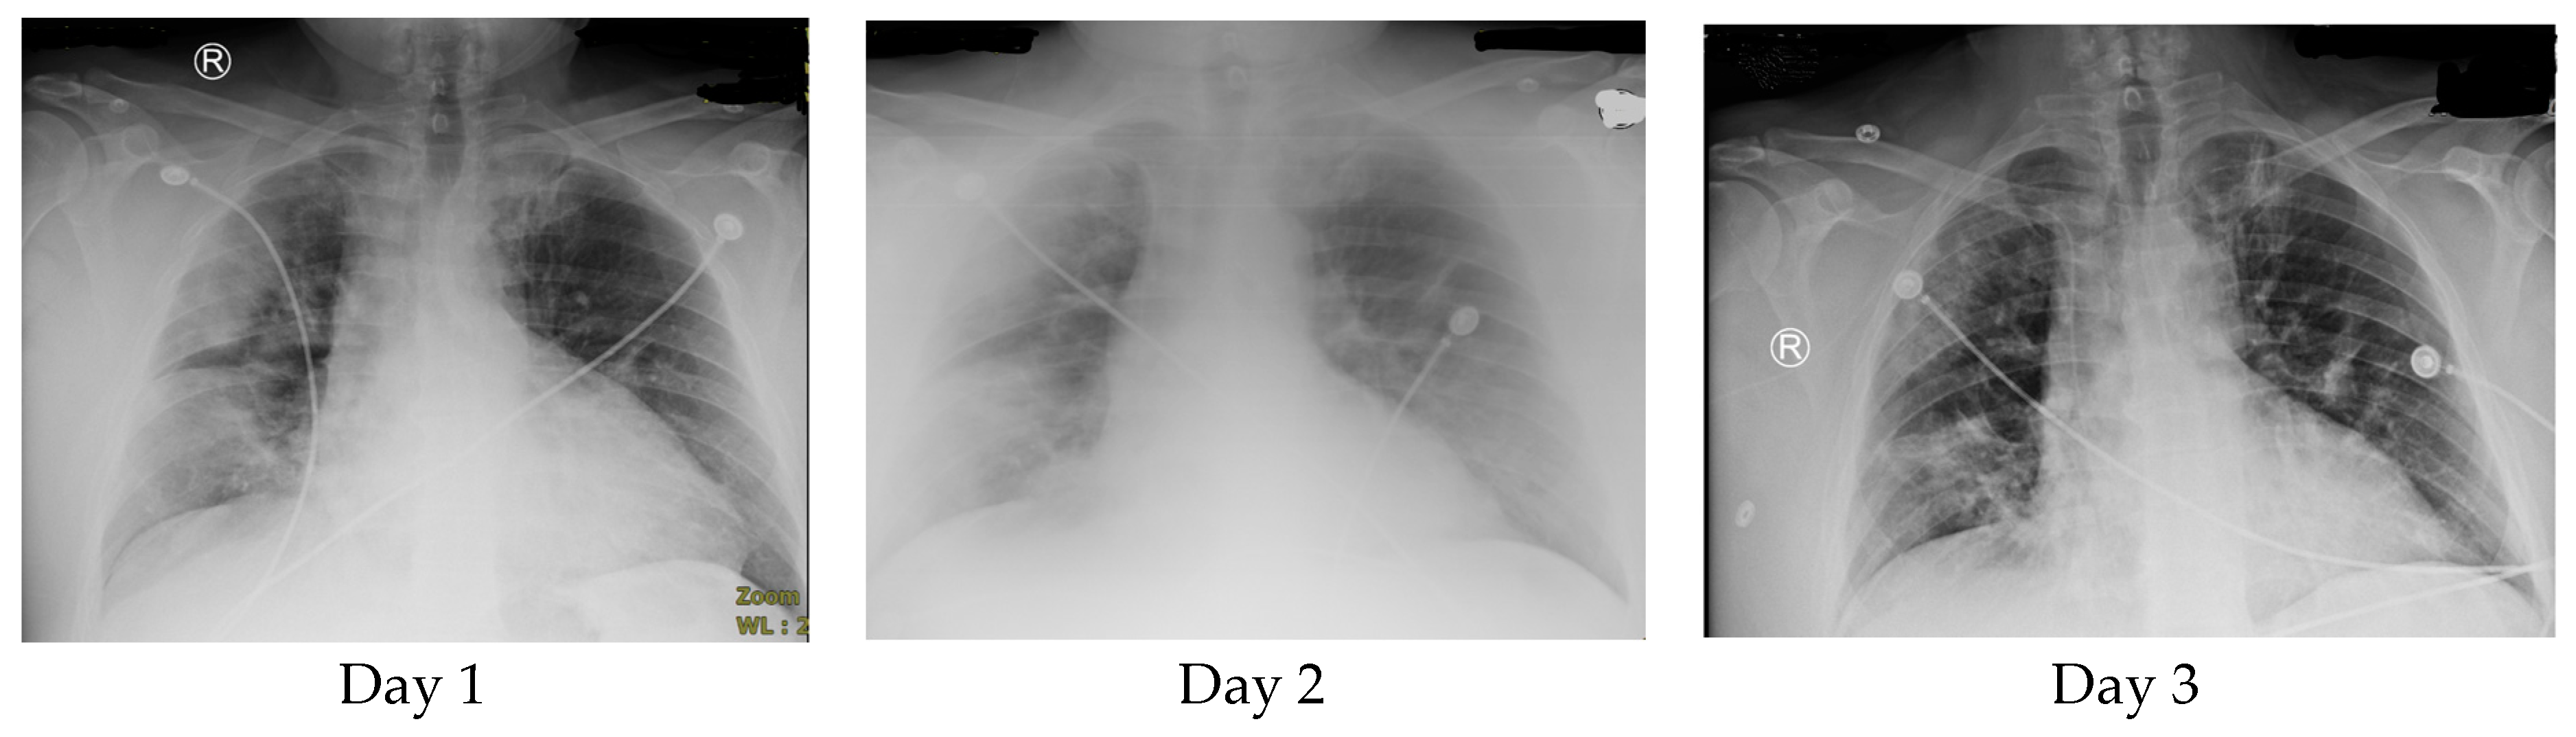

On day 5, the patient was stable and experienced only mild shortness of breath and no other complaints. He was still on a non-rebreather at 50%. The O2 saturation was 96%. The acute phase reactant levels remained elevated, but most values showed improvement (D-dimer 1093, ESR 40, and CRP 3.6 (representing a decrease), and ferritin 682 (representing an increase from the previous day)). The lymphocyte count was 1.3. ALT was elevated (54), and AST was normal (29). The WBC level was 14.2. A chest X-ray revealed diminished infiltrates as patchy opacities compared with imaging on day 2 (Figure 1).

Figure 1.

Chest X-rays on day 1, day 2, and day 5. Tocilizumab was administered as two doses of 500 mg Q12 (during the night of day 1 and the morning of day 2).